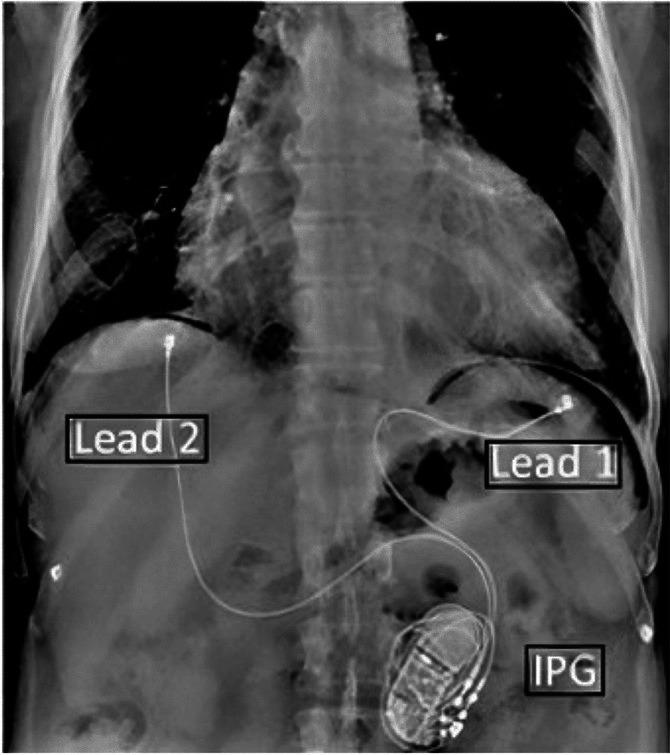

对于中度至重度心力衰竭,最大耐受性药物治疗与永久性机械循环支持和/或心脏移植或姑息性治疗之间存在差距,这代表了服务不足的患者群体。新的治疗方法正在发展,不仅可以改善这些患者的生活质量,还可以改善血液动力学,并有可能逆转疾病的进展。这篇综述的重点是一种这样的治疗,同步膈肌刺激。目前的临床结果表明,在6-12个月的治疗中,患者的运动耐受性、生活质量和血流动力学功能得到改善,可以通过微创腹腔镜手术安全地实施,通常作为门诊。该技术已被授予突破性设备称号,并正在接受美国食品和药物管理局的双盲随机对照试验评估。

The gap between maximally tolerated medical therapy and consideration for permanent mechanical circulatory support and/or cardiac transplant or palliative treatment of moderate to severe heart failure represents an underserved patient population. New therapies are evolving which may not only improve quality of life for these patients but also improve hemodynamics and potentially reverse the progression of the disease. This review is focused on one such therapy, synchronized diaphragmatic stimulation. Current clinical results suggest that patients experience improved exercise tolerance, quality of life, and hemodynamic function over 6-12 months of therapy which can be safely implemented through a minimally invasive laparoscopic procedure, often as an outpatient. This technology has been granted breakthrough device designation and is being evaluated for a double-blinded, randomized controlled trial by the US FDA.